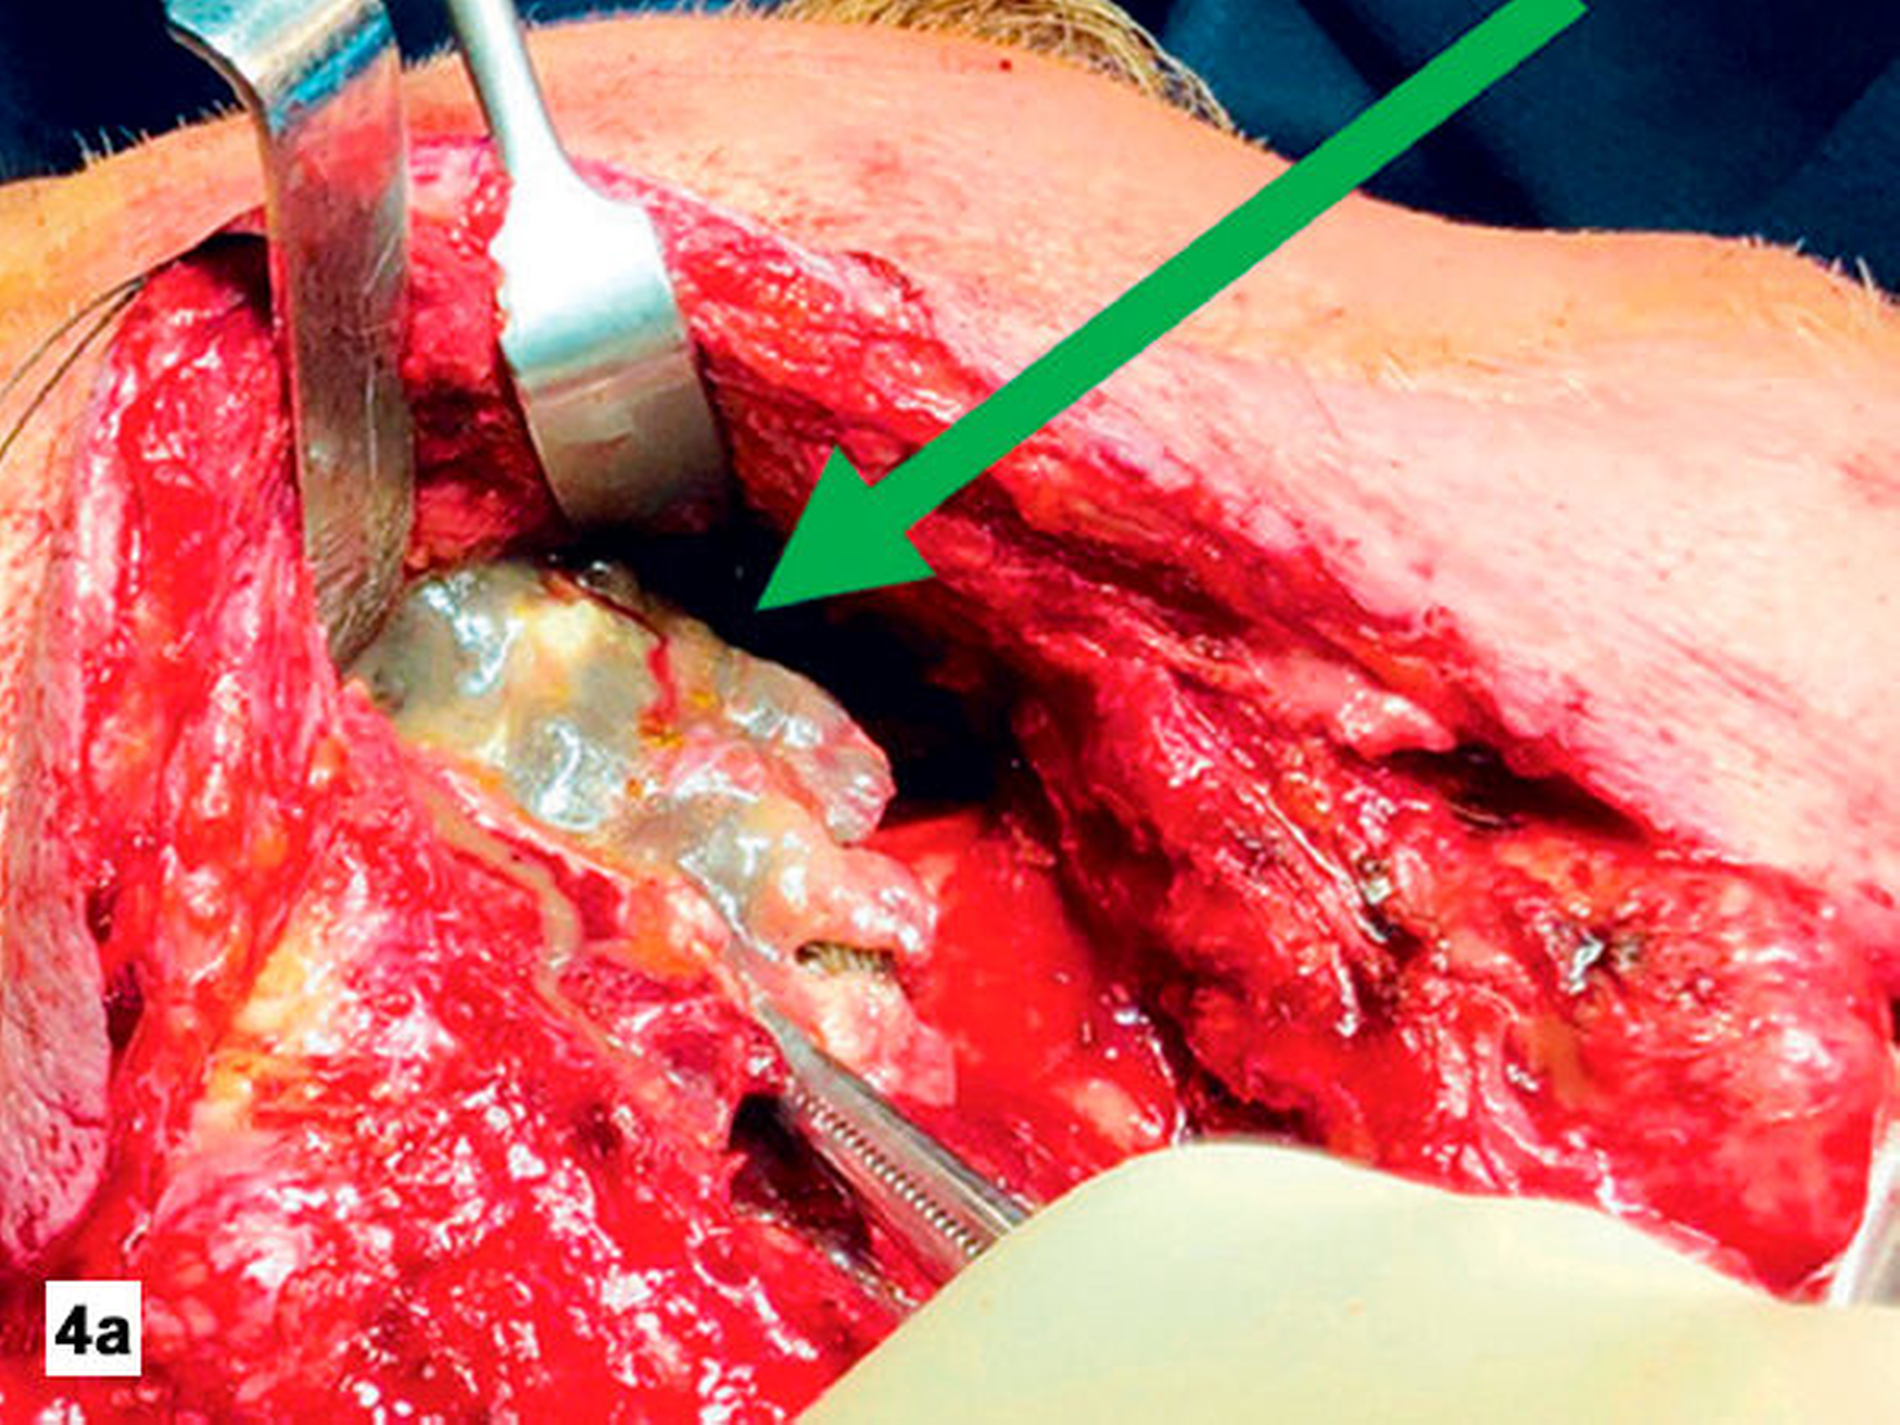

Am Folgetag wurde eine erneute chirurgische Exploration durchgeführt, hier zeigten sich weitere Nekrosefelder (Abbildung 4). Ein erneutes Debridement und Lavagen wurden durchgeführt. In den nächsten Tagen stabilisierte sich der Patient kardiopulmonal und die Entzündungsparameter waren rückläufig. Es erfolgte noch zweimal eine chirurgische Exploration, hierbei mussten nur noch wenige Nekroseareale abgetragen werden und der Wundgrund befand sich zunehmend in sauberer Granulation (Abbildung 5).